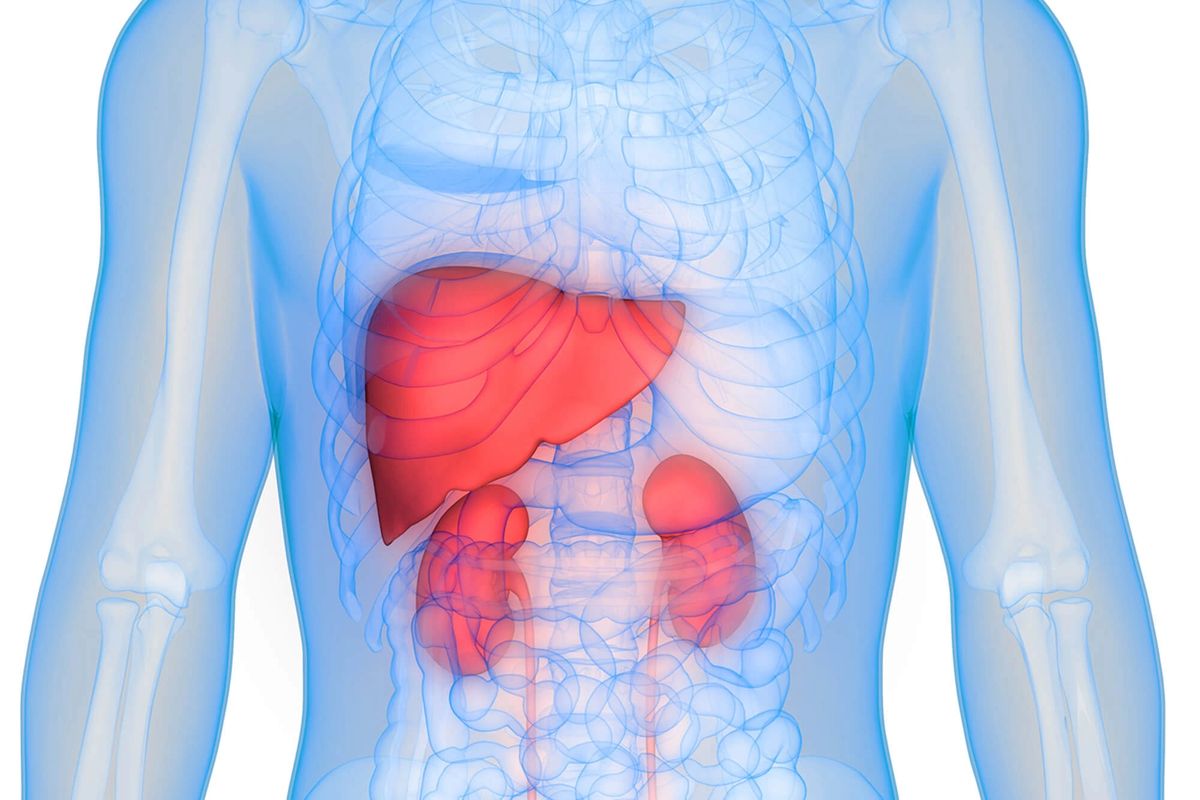

The urinary system, also called the “genitourinary system”, is in charge of producing, storing and releasing urine. Metabolic wastes are also eliminated via the organs of the urinary systems, which can also keep the appropriate levels and concentrations of water, nutrients, salts, and nitrogenous wastes inside our body, and consequently participate in preserving homeostasis. These processes run through a series of organs, tubes, nerves and muscles allowing the urinary system to control erythrocyte formation and blood volume. The genitourinary system works through a cooperation among the kidneys, lungs, intestines and skin. In males and females, the urinary system and reproductive system are developmentally and anatomically related.

There are two kidneys in the human body, each is fist-sized, and both are located in the abdomen, on either side of the spine, right behind the rib cage (Fig. 1). They span from T12 to L3. Each kidney is approximately three vertebrae in length. When interpreting radiographs, this can be operated to assess any change in size. The right kidney is observed somewhat lower due to the influence of the liver (Fig. 2). The body's circulation is cleared of water-soluble wastes by the kidneys, which act to keep blood pressure, pH levels, electrolyte concentrations, and the quantity of extracellular fluid, and consequently they maintain homeostasis in the body. Urea and uric acid are the main waste products managed by the urinary system. When these products are excessively piled up, severe diseases occur. Blood is purified through filtration, reabsorption, and secretion. These processes are accomplished by the nephrons in each kidney (Fig. 3). There are thousands of nephrons in the kidneys; each is supported by a filtration mechanism called the renal corpuscle, containing a glomerulus and a Bowman's capsule. To evaluate how well the kidneys are working, the glomerular filtration rate is examined. Kidneys are designed with external and internal structures.